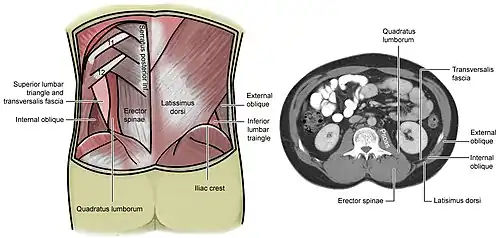

Surface anatomy of the back

Surface anatomy of the back -

Lumbar triangle

Lumbar triangle